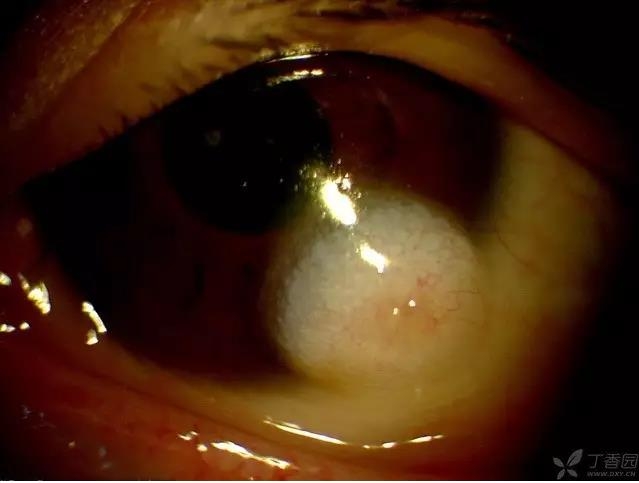

▼角膜皮样瘤

实用贴:眼科病例高清图片

▼角膜皮样瘤(不同的患者,弥散光照明)